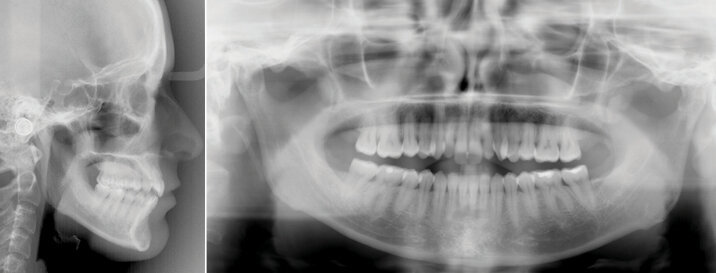

Konečná foto a RTG dokumentace